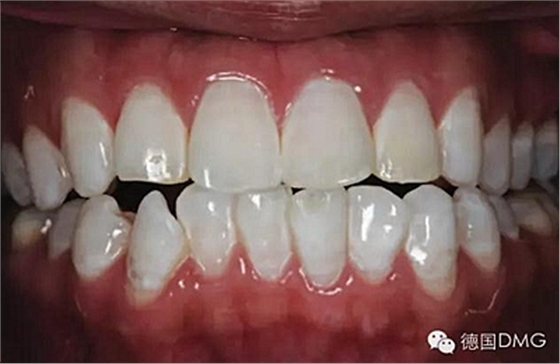

一28歲女性患者來我院修復(fù)科就診,主訴為前牙嚴(yán)重的牙齒著色和缺損十余年,要求改善牙齒的美觀。臨床檢查表明該患者有重度氟斑牙,極大的影響了前牙美學(xué)。

考慮到患者為年輕人,保守治療方法比傳統(tǒng)侵入性治療手段更為合適。術(shù)前牙周治療預(yù)防牙齦炎癥和改善牙齦健康狀態(tài),隨后聯(lián)合采用釉質(zhì)打磨、牙漂白和樹脂滲透來處理牙釉質(zhì)表面。

5、由于氟斑牙存在釉質(zhì)礦化不全等問題,家庭漂白兩周后,使用標(biāo)準(zhǔn)的樹脂滲透技術(shù) (Icon, DMG Products, Hamburg. Germany) 來預(yù)防釉質(zhì)齲。最后,徹底改變患者的前牙美學(xué),并在一年后仍保持穩(wěn)定。